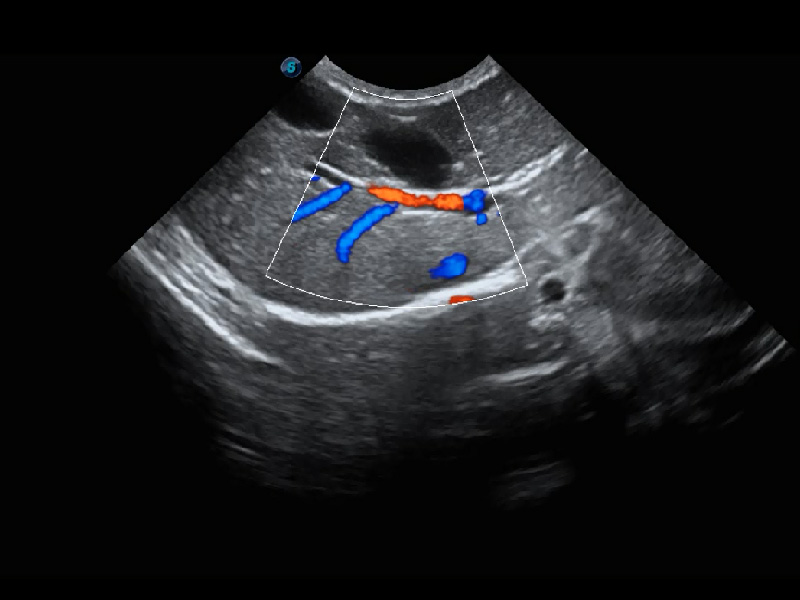

4T血流成像 微察秋毫

融合不同血流成像技术的优势,即可以提升血流成束性,同时可提高血流的视觉敏感性。

PDI 能量多普勒血流

提供高灵敏度和空间分辦率的血流图像,获得更加真实和丰富的诊断信息。

SR Flow 高分辨率血流成像

能够清晰显示细小、低速血流图像,获取传统彩色多普勒技术难以得到的细节和信息。

Micro F 显微血流成像

通过创新的Matrix E自适应滤波器和超长时间域算法,极大提升超低速微细血流的检出能力,同时更精准地滤除软组织和噪声信号,为兽用医生提供以往无法通过常规血流获得的疾病诊断信息。

Bright Flow 立体血流成像

在传统二维血流成像的基础上,呈现血流的立体感,具有动感的生命力之美。精确区分不同血管的空间关系,提高了血流的视觉敏感性。

(犬)肾脏血流